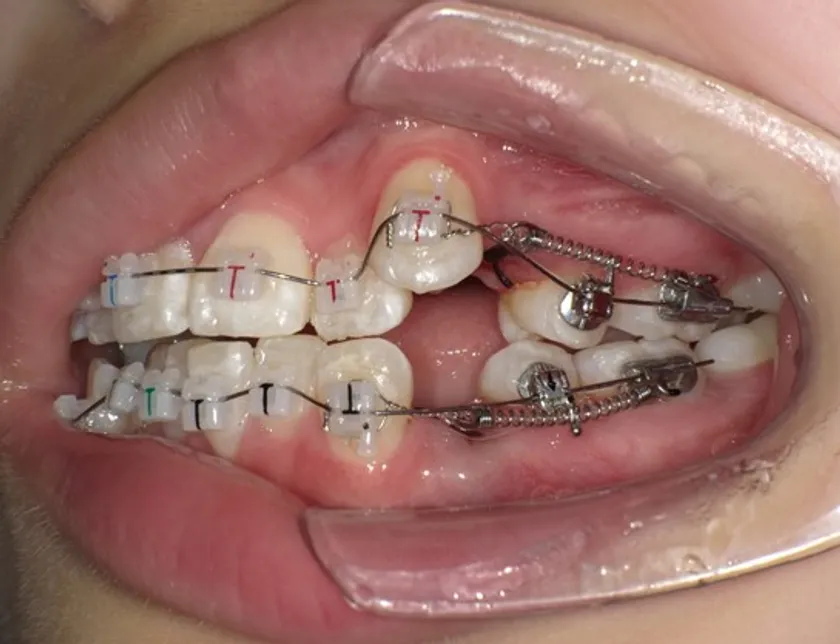

患者は13歳8か月の女子。主訴は左上に八重歯があること。上顎両側、下顎左側第一小臼歯を同時抜歯し、JET systemで治療を行ったところ動的治療期間は7か月であった。前歯部のトルクコントロール、上下顎正中の一致、咬合関係の改善が行われた。抜歯により誘発されたRAPを利用したJET systemでの治療は、治療期間の短縮に寄与し、患者QOLを向上させることが示唆された。

装着時